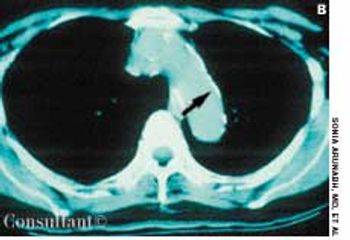

For 2 months, a 31-year-old woman had had dyspnea anddull, continuous retrosternal pain. She was admitted to thehospital, and a helical CT scan of the thorax identified asaddle pulmonary embolism. An ultrasonogram revealeddeep venous thrombosis (DVT) in the left leg. Intravenousheparin was given; the patient was discharged,and warfarin was prescribed.